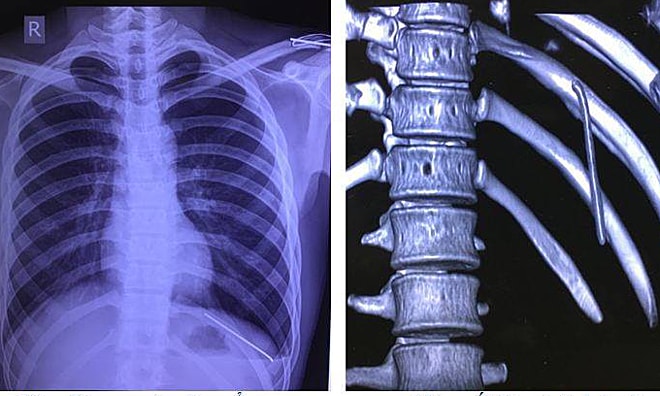

The nail moved from the shoulder to the lung of an 18-year-old boy.

The kirschner nail was used by doctors to perform a clavicle fusion surgery on the patient 7 months ago.